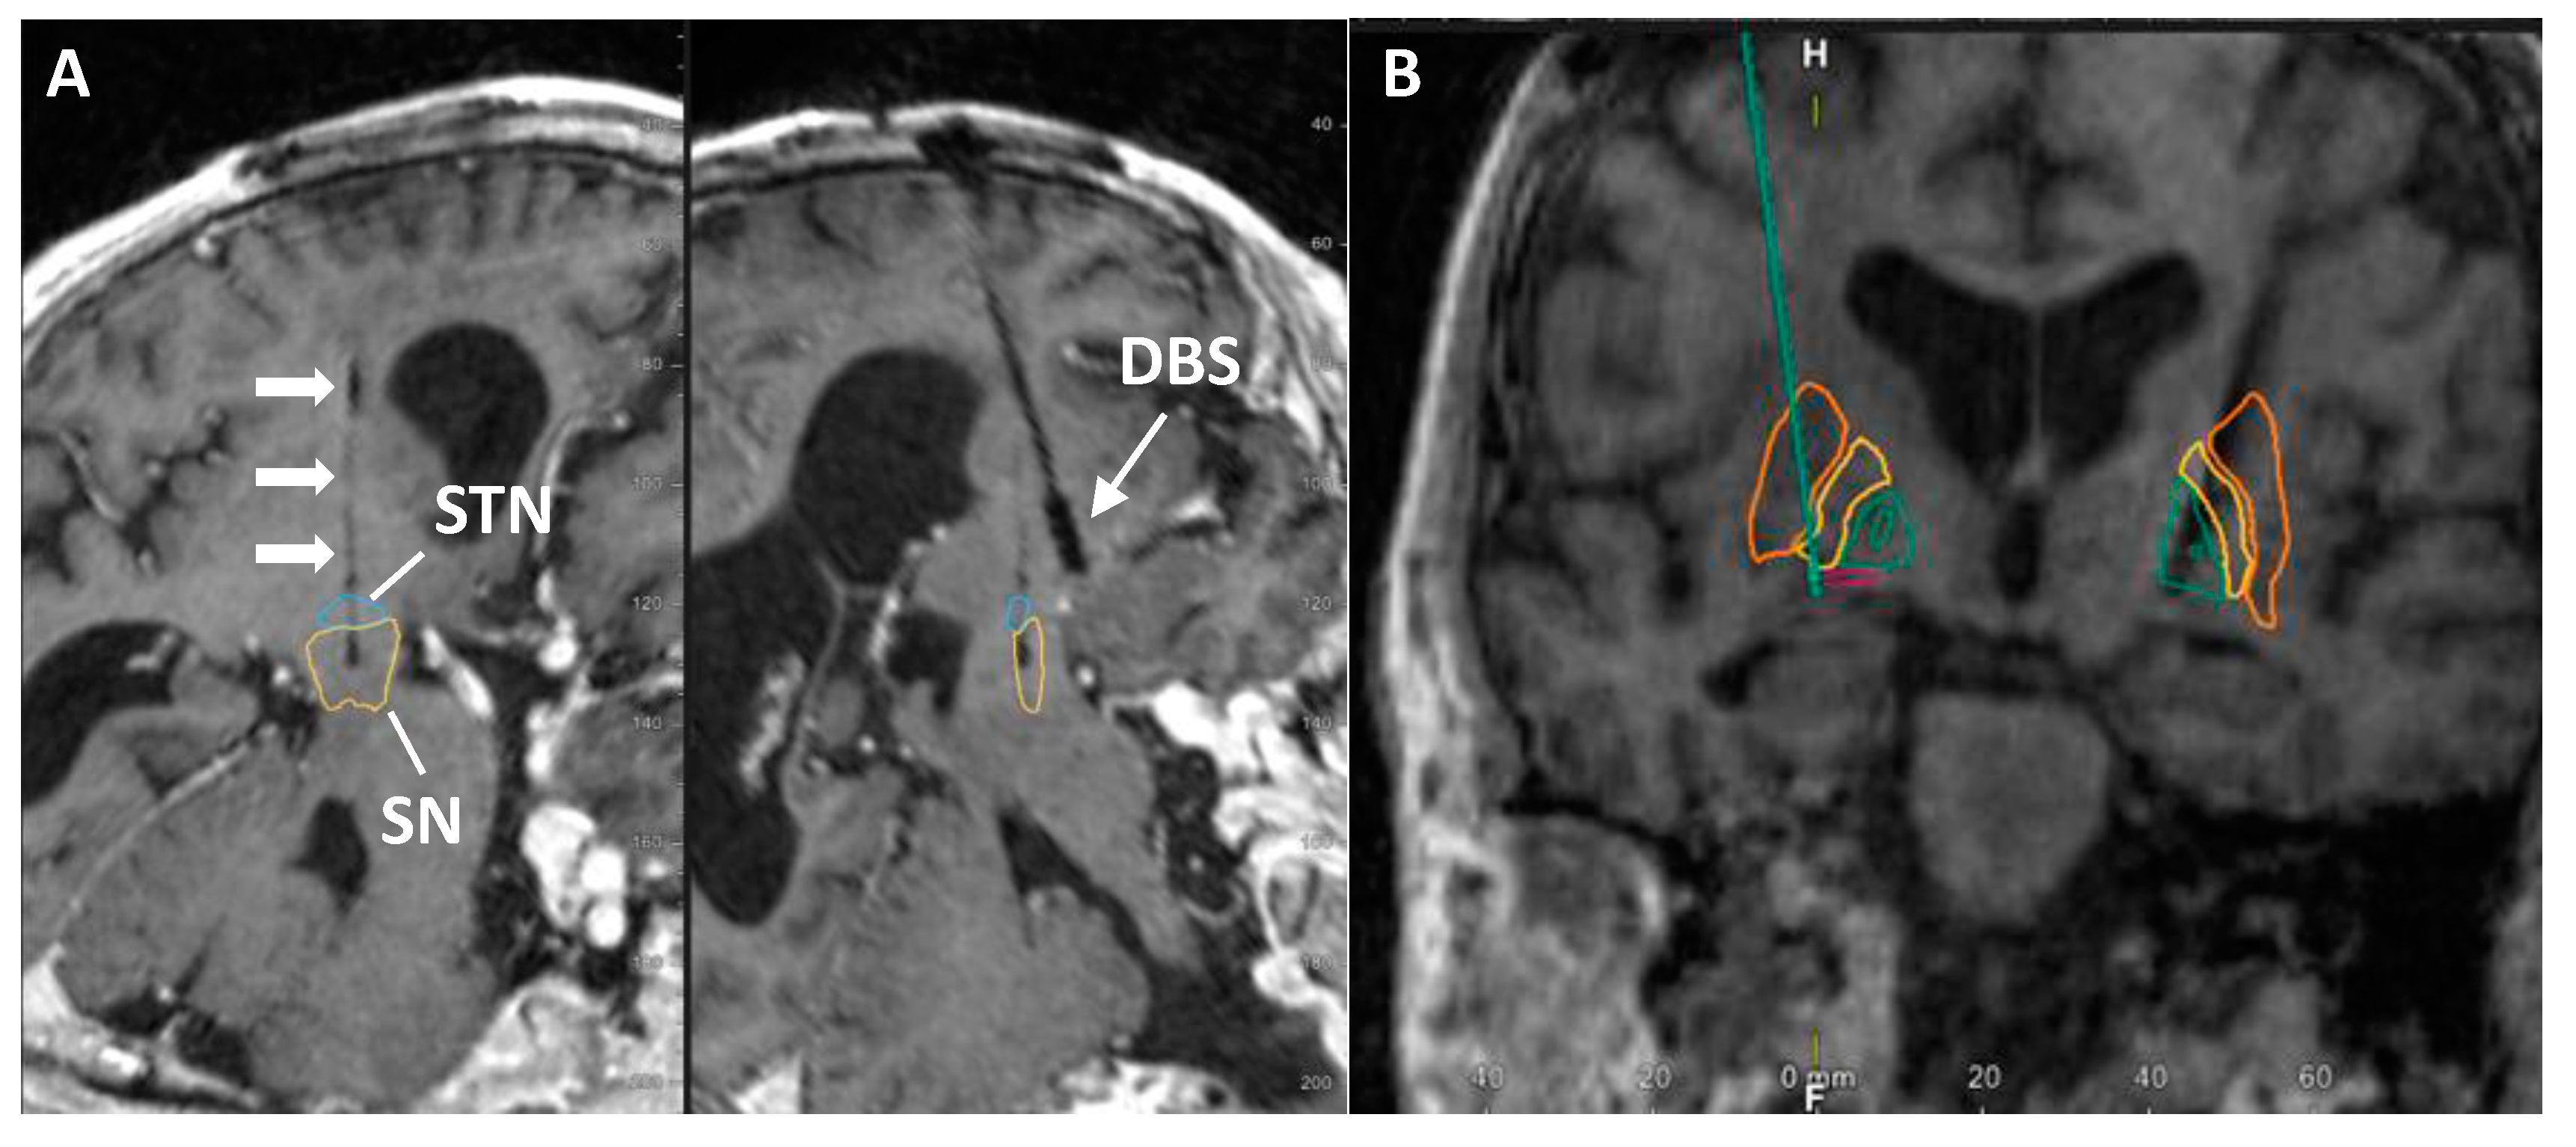

- Van Horne, C.G.; Quintero, J.E.; Slevin, J.T.; Anderson-Mooney, A.; Gurwell, J.A.; Welleford, A.S.; Lamm, J.R.; Wagner, R.P.; Gerhardt, G.A. Peripheral nerve grafts implanted into the substantia nigra in patients with Parkinson’s disease during deep brain stimulation surgery: 1-year follow-up study of safety, feasibility, and clinical outcome. J. Neurosurg. 2018, 129, 1550–1561. [Google Scholar] [CrossRef]

- Quintero, J.E.; Slevin, J.T.; Gurwell, J.A.; McLouth, C.J.; El Khouli, R.; Chau, M.J.; Guduru, Z.; Gerhardt, G.A.; van Horne, C.G. Direct delivery of an investigational cell therapy in patients with Parkinson’s disease: An interim analysis of feasibility and safety of an open-label study using DBS-Plus clinical trial design. BMJ Neurol. Open. 2022, 4, e000301. [Google Scholar] [CrossRef]